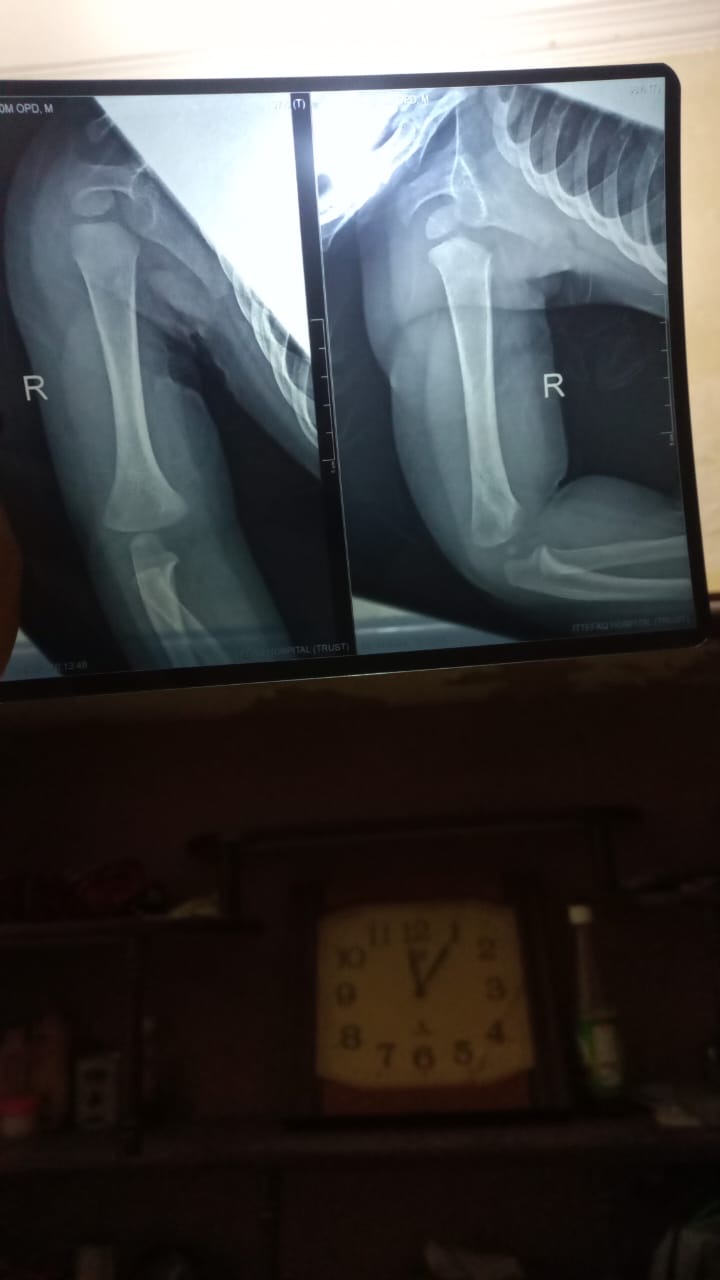

My Child Fell from Bed, and we went to childeren hospital in lahore, they ask for Xray and after analysing they said its a minor fracture that does not need any plaster, Later we went to Ittefaq Hospital, and their dr asked for new Xray, he also said their is fracture in Arm, So it needs to be plaster. What i am unable to understand is the price the asked for it, Dr said it will take 50 to 60K for Plaster. Does is it really cost that much??. i have shared Xrays, Kindly comment your thought !. Thanks,

minor fracture ha .50k ma to surgery hojati ha.plaster 4k tk hojaega maximum